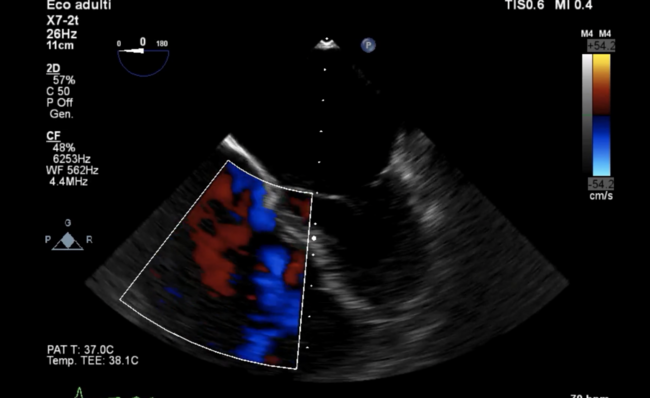

The preprocedural cardiac magnetic resonance (CMR) showed a right ventricular end-diastolic volume index (RVEDi) of 79 mL/m2, right ventricular end-systolic volume index (RVESi) of 27 mL/m2, tricuspid regurgitant volume (TRV) of 56 mL, and tricuspid regurgitant fraction (TRF) of 67% (Figure 3). Due to the patient's history of breast cancer radiotherapy and high surgical risk, the heart team preferred a transcatheter approach as the treatment option. The first TriClip (Abbott Vascular) was successfully implanted in the anteroseptal commissure, determining annulus size reduction and the subsequent necessity of transesophageal echocardiographic projection change to assess the result due to acute reshaping (Figure 4 and Figure 5; Video Series). A second TriClip was implanted in the anteroseptal commissure, highlighting the changes in the valvular plane and cardiac axis (Video Series). Residual TR was trivial (Video Series). The acute remodeling was confirmed at the CMR follow-up (Figure 6), with significant volume and TR reductions (RVEDi, 39 mL/m2; RVESi, 18 mL/m2; TRV, 8 mL; and TRF, 23%).